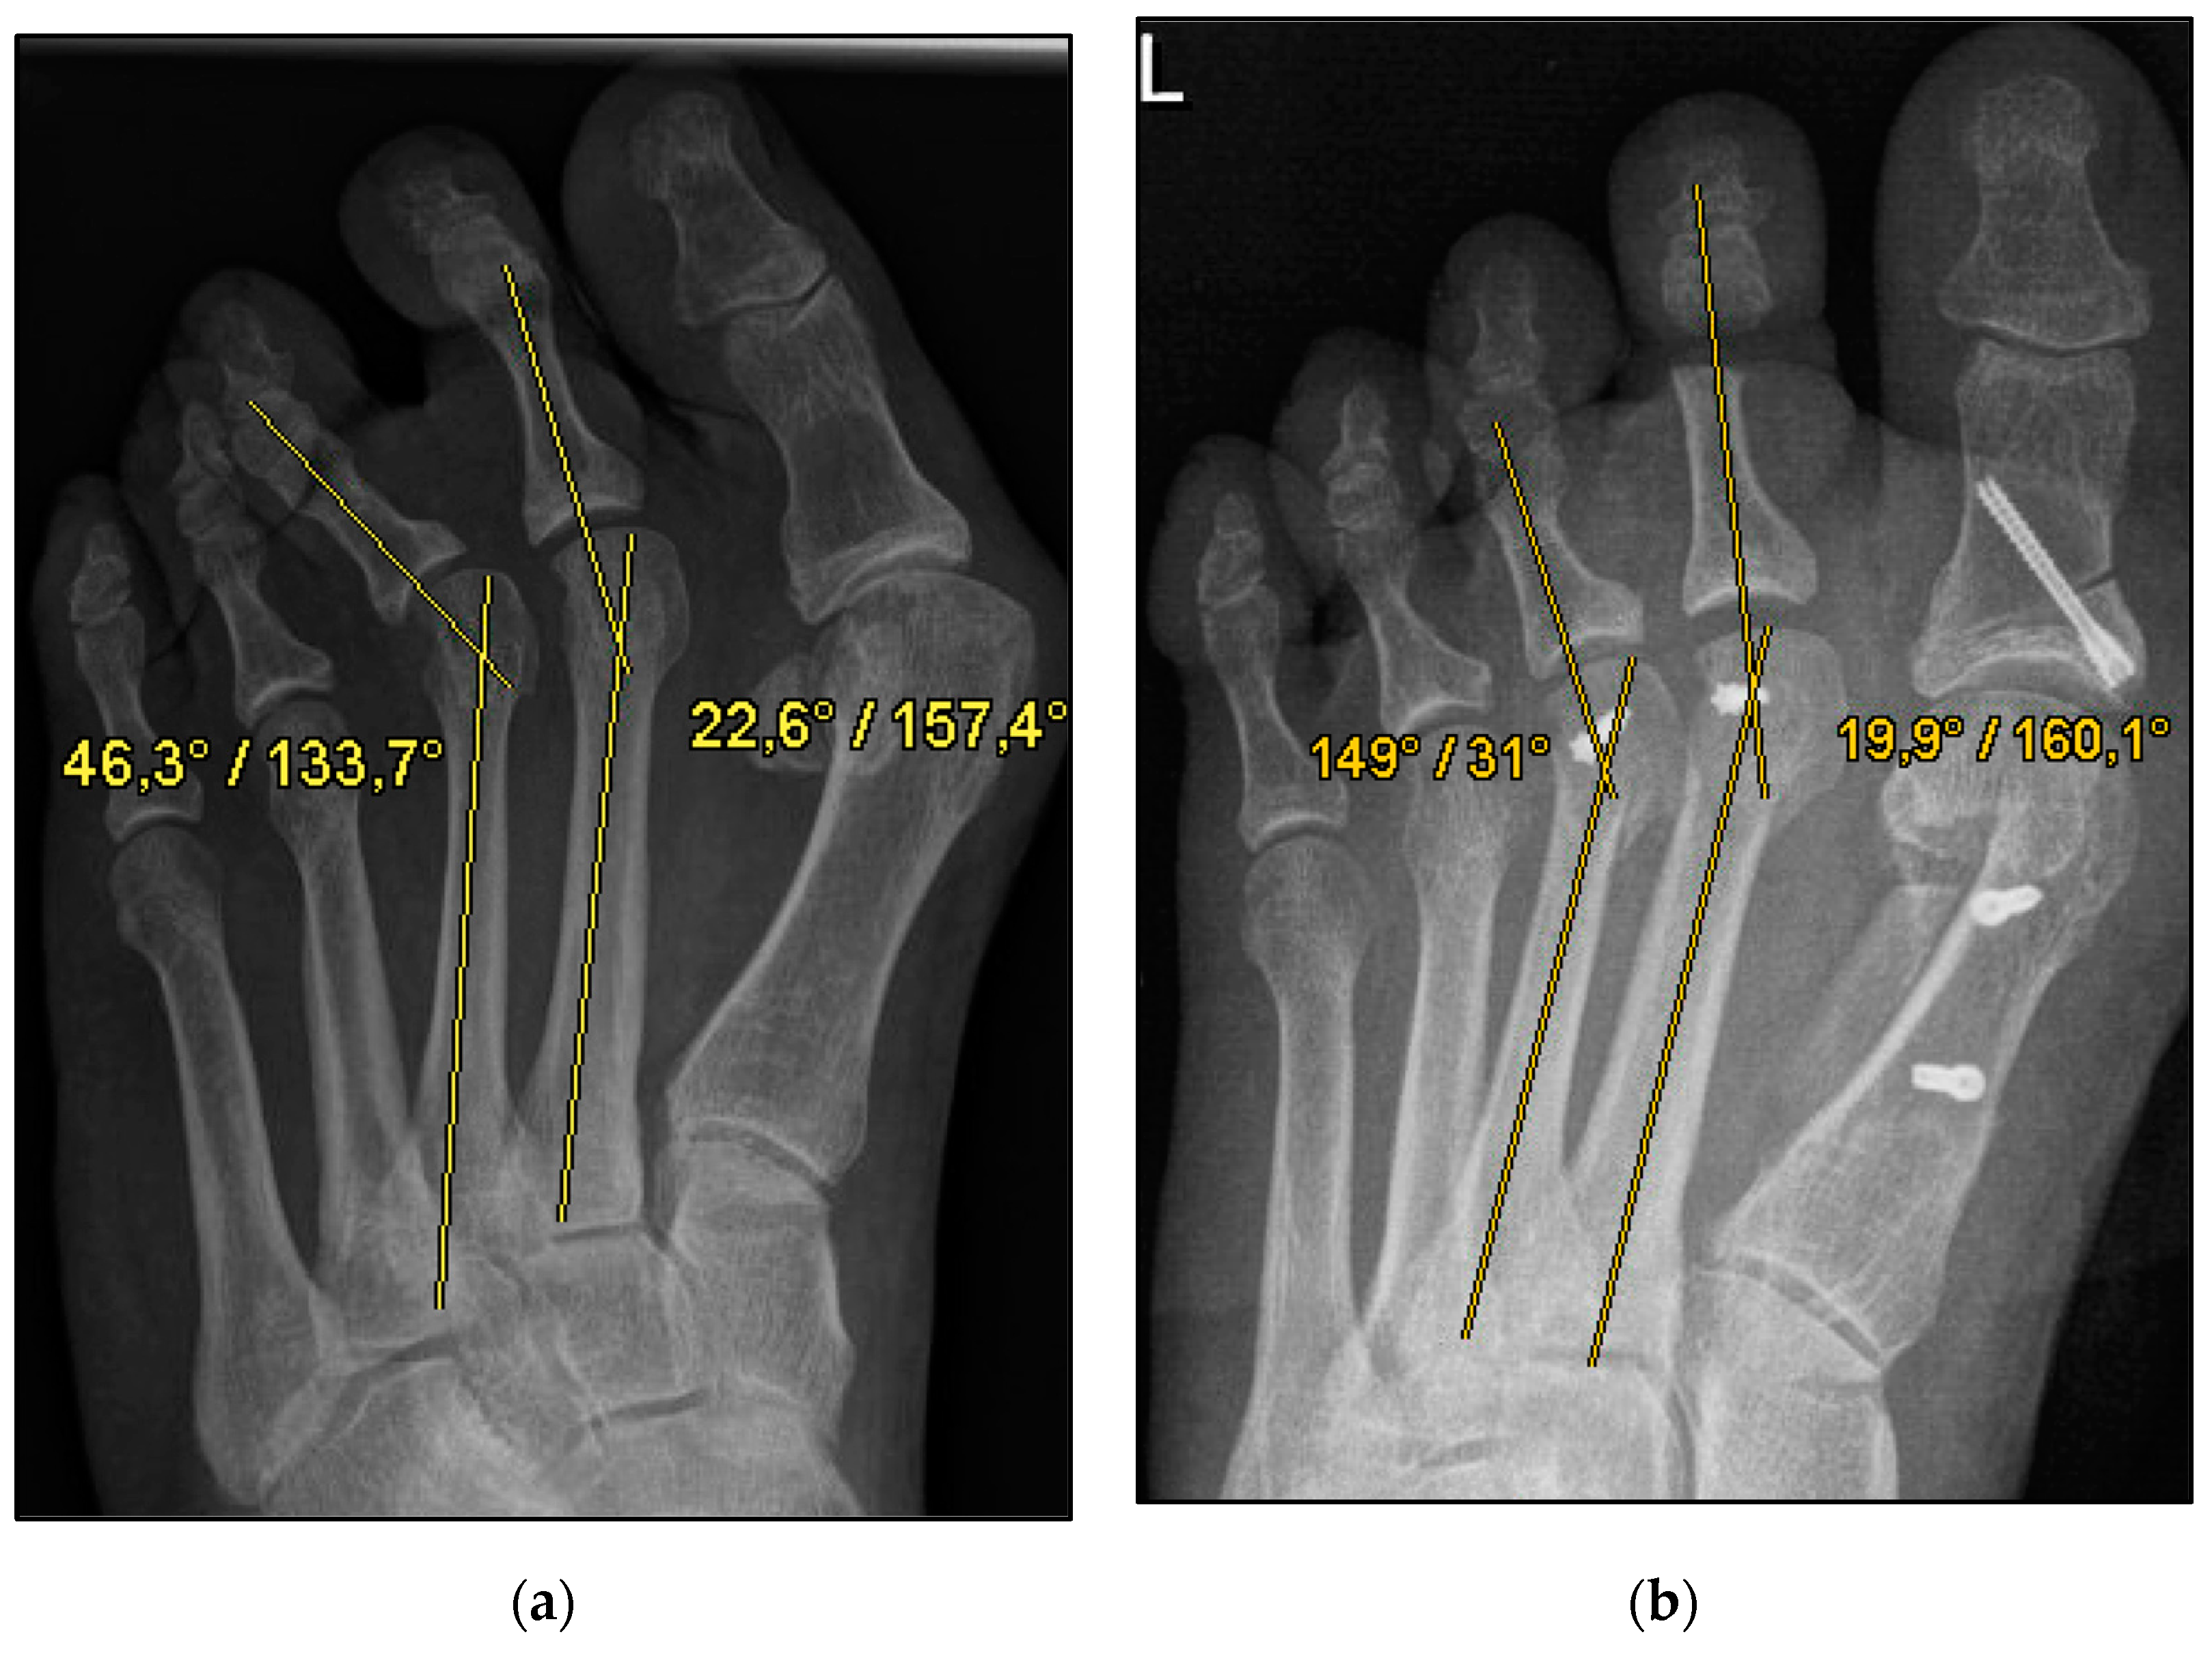

Figure 1.

Pre- and postoperative radiographic results of combined hallux valgus surgery and Weil osteotomy of metatarsal 2 and 3 (group A with screw), left foot. (a) Weight-bearing radiograph: anteroposterior view preoperative, (b) weight-bearing radiograph: anteroposterior view, 6 weeks postoperative.

We aimed to show that conventional open Weil osteotomy has an equally high correction potential regarding transverse plane alignment, even without screw fixation. (Figure 1 and Figure 2) For this purpose, the pre-, intra-, and weight-bearing postoperative radiographs after Weil osteotomy with and without screw fixation were compared. In addition, the radiographs were evaluated with regard to the metatarsophalangeal angle, malalignment, and delayed union and nonunion. This radiological study explicitly aimed to reveal a possible loss of correction after the bony union. The clinical results will be evaluated separately.

The underlying assumption of our study and the knowledge gained from our results can be further elaborated upon. An inharmonious transverse plane alignment can also be corrected with Weil osteotomy and does not require osteosynthetic fixation of the displaced metatarsal head [24]. The results confirm, based on postoperative weight-bearing radiographs, that the surgically induced correction is maintained regardless of screw fixation. An objectifiable criterion was the metatarsophalangeal angle measured pre- and postoperatively using weight-bearing radiographs in the dorsoplantar view (Figure 1 and Figure 2). In both treatment groups, it was possible to bring the maximum axis deviation closer to the mean value; the mean difference between pre- and postoperative metatarsophalangeal angle was only 3.8°. On average, 10.6 degrees were required to achieve the desired surgical result, regardless of screw fixation (Figure 4 and Figure 5). However, the significantly higher possibility of viewing the affected metatarsal joint space postoperatively can also be considered a successful outcome of the restoration without screw fixation. The visibility of the articular surface, in turn, proves the centering of the metatarsal head in the transverse plane as well as a sufficient correction in the sagittal plane (Figure 6 and Figure 7) [25]. Again, the inability to view the joint space indicates that inadequate correction of the claw toe deformity as well as the metatarsal, which was considered “too long”, was performed [1,14,26].